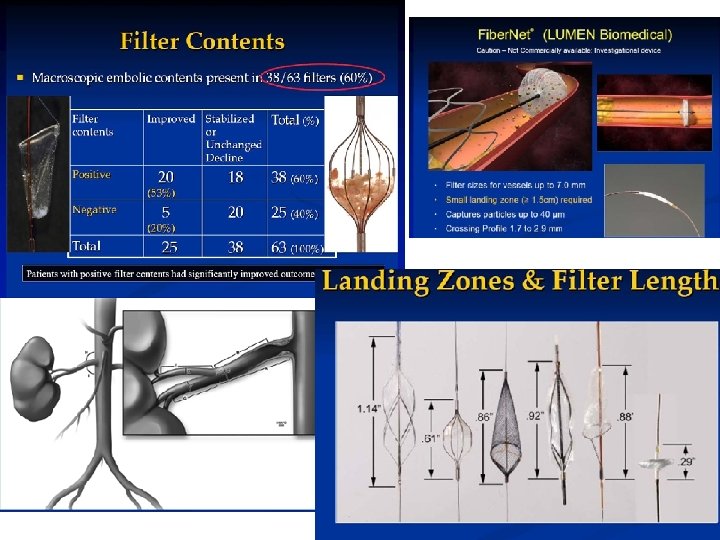

За 30 летную историю почечной ангиопластики: 1. Постоянное совершенствование техники операции 2. Инструментов: проводниковые катетеры, проводники, баллонные катетеры, стенты, длинные доставляющие системы 5 -6 F 3. Использование радиального и феморального доступа с ушивающим устройством. 4. Использование противо эмболических фильтров 5. Использование FFR технологии для объективизации степени сужения почечной артерии

За 30 летную историю почечной ангиопластики: 1. Постоянное совершенствование техники операции 2. Инструментов: проводниковые катетеры, проводники, баллонные катетеры, стенты, длинные доставляющие системы 5 -6 F 3. Использование радиального и феморального доступа с ушивающим устройством. 4. Использование противо эмболических фильтров 5. Использование FFR технологии для объективизации степени сужения почечной артерии